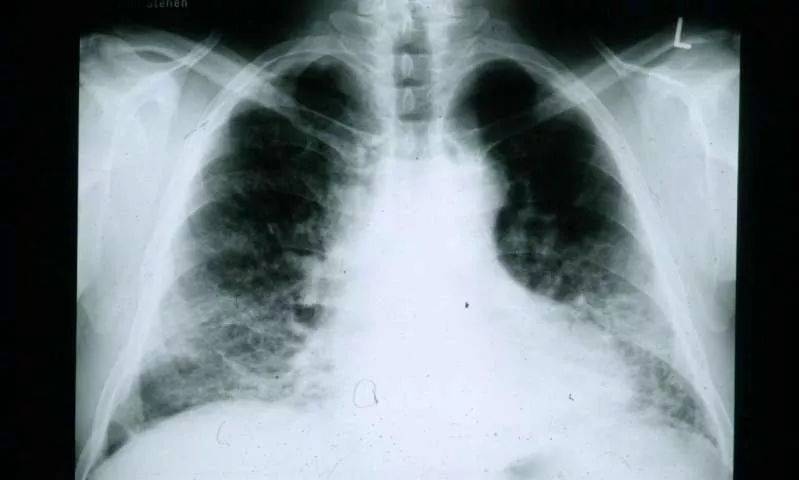

如何防止重症、危重症病例后期形成肺纤维化?

新冠肺炎是急性的病毒性传染病,病程比较短,所以导致肺纤维化发生发展的概率比较低,尤其是轻型的病例,大部分不会出现肺纤维化。对重症和危重症病例,有可能会出现肺纤维化。

一方面,出院后要通过康复手段,包括中医中药等,进行相应的干预,避免后遗的纤维化发生发展等等。

另一方面,进行密切的监测随访,对重症、危重症的出院患者要长期随访,因为纤维化的发生发展不是短期内发生的,可能需要一段时间,所以强调对重症和危重症的出院患者要长期随访,观察可能发生的问题,及时进行干预。